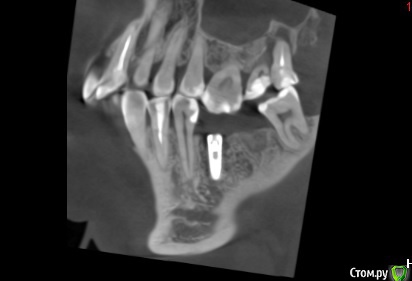

Andre_ Опубликовано 16 июня, 2015 Автор Поделиться Опубликовано 16 июня, 2015 Шурупить в синус, немного делая закрытый, буду через пару недель, если не считать косячной отслойки, можно сказать, что всё успешно. Открывать шуруп - в ближайшие дни (прокрутится или нет вместе с ФДМ, интересно ) Ссылка на комментарий

Имплантатор Опубликовано 29 июня, 2015 Поделиться Опубликовано 29 июня, 2015 Хм... Не вижу смысла в синусе вообще. 6 мм высоты достаточно. Можно просто имплантатом закортикалиться на 1 мм. С таким-то расстоянием до окклюзионной... 1 1 Ссылка на комментарий